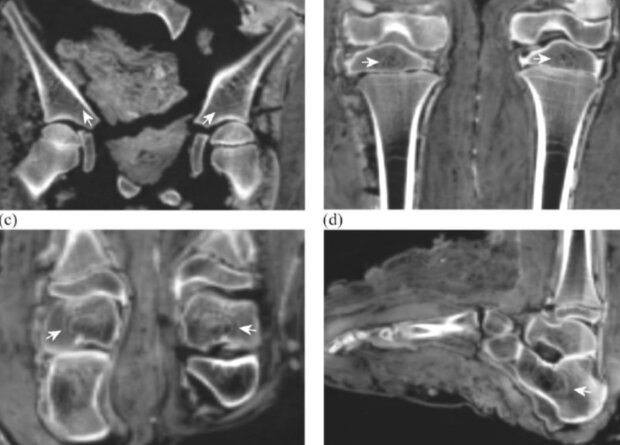

Палеопатологи исследовали с помощью компьютерной томографии 21 древнеегипетскую детскую мумию. Они обнаружили на костях большинства индивидов многочисленные свидетельства задержек роста – линии Гарриса и гиперостоз. Кроме того, ученые впервые зафиксировали с помощью методов палеорадиологии, что древний египтянин отравился свинцом. Им оказался мальчик, который умер в возрасте семи–девяти лет. Об этом сообщается в статье, опубликованной в International Journal of Osteoarchaeology.

Развитие палеорадиологии, то есть исследований биоархеологических материалов с помощью современных методов визуализации – рентгенографии, компьютерной и магнитно-резонансной томографии, трехмерной реконструкции и некоторых других технологий, внедренных в медицинскую практику в конце минувшего столетия, позволило ученым существенно продвинуться в изучении древних мумий. Дело в том, что традиционное патолого-анатомическое исследование мумифицированных тканей не только приводит к порче важных находок, но и физически трудно выполнимо из-за сухости и жесткости таких останков. Напротив, палеорадиология позволила узнать многое о жизни и смерти древних людей, например, об Этци, подробно прочитать о котором можно в нашем материале «Из пропасти во льду».